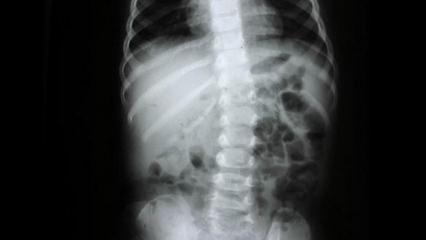

Omurga sağlığı için nelere dikkat edilmeli? Uzman isim açıkladı